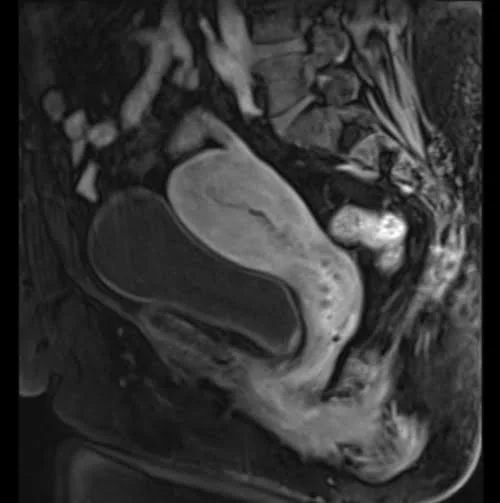

Gynae pelvis (Large abdominopelvic Mass)

Gynae pelvis (ovarian ca/adnexal mass protocol)